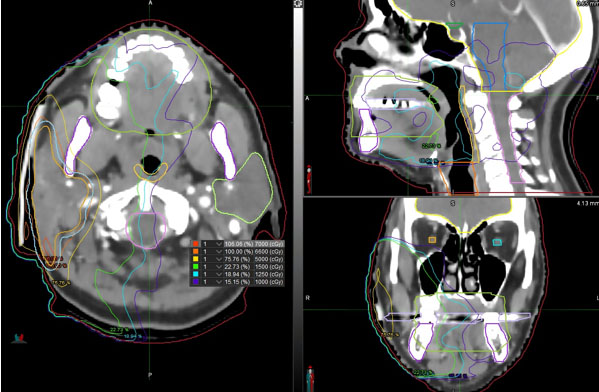

Magnetic resonance imaging should be the imaging method of the first choice. It is efficient in verifying suspected malignancy and can provide extensive anatomical information regarding the primary tumor’s location and its relationship to the FN and surrounding tissues [3],[4]. In addition to the well-known signs of parotid malignancy, such as poorly defined borders, large tumor size with noticeable invasiveness, irregular shape, infiltration of extra-parotid lymph nodes, and low to moderate signal intensity on T2-weighted images, relatively large tumors with central necrosis is a useful imaging feature of SCC originating in the parotid gland (Figure 1) [5],[6].

Figure 1: A 62-year-old male with primary parotid squamous cell carcinoma in the left parotid gland. Magnetic resonance images were acquired using a 3.0 T MRI machine. Axial T2WI (A) and T1WI (B) show an irregular mass involving the left parotid gland and masseter muscle, with the tumor showing a slightly low signal and multiple small focal areas of markedly high signal on T2WI (arrow). Enhanced axial (C) and coronal (D) T1WI show inhomogeneous enhancement with necrotic areas in the center (arrow).